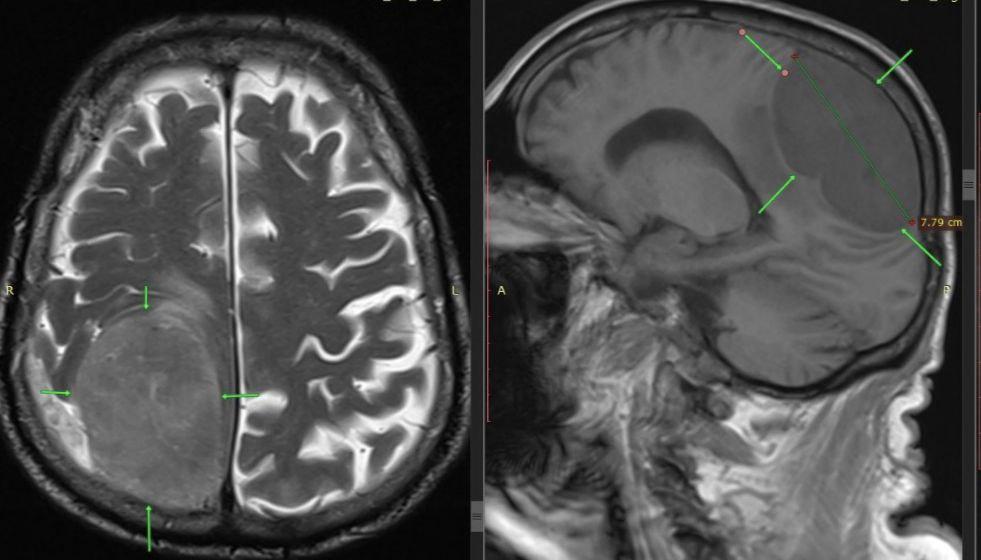

85-летний ставрополец обратился за помощью, когда у него перестала функционировать левая нога и вся левая сторона тела. Изначально симптомы указывали на инсульт, но экстренное обследование выявило истинную причину – гигантскую опухоль диаметром 8 на 7 сантиметров. Новообразование располагалось в правой теменно-затылочной области мозга, контролирующей движения левой половины тела.

Нейрохирурги выполнили трепанацию черепа и полностью удалили опухоль. Операция завершилась успешно, двигательные функции левой стороны тела у пациента восстановились, а мозг вернулся к своему нормальному положению.

Хирурги извлекли из головы пациента новообразование, сравнимое по величине с лимоном.